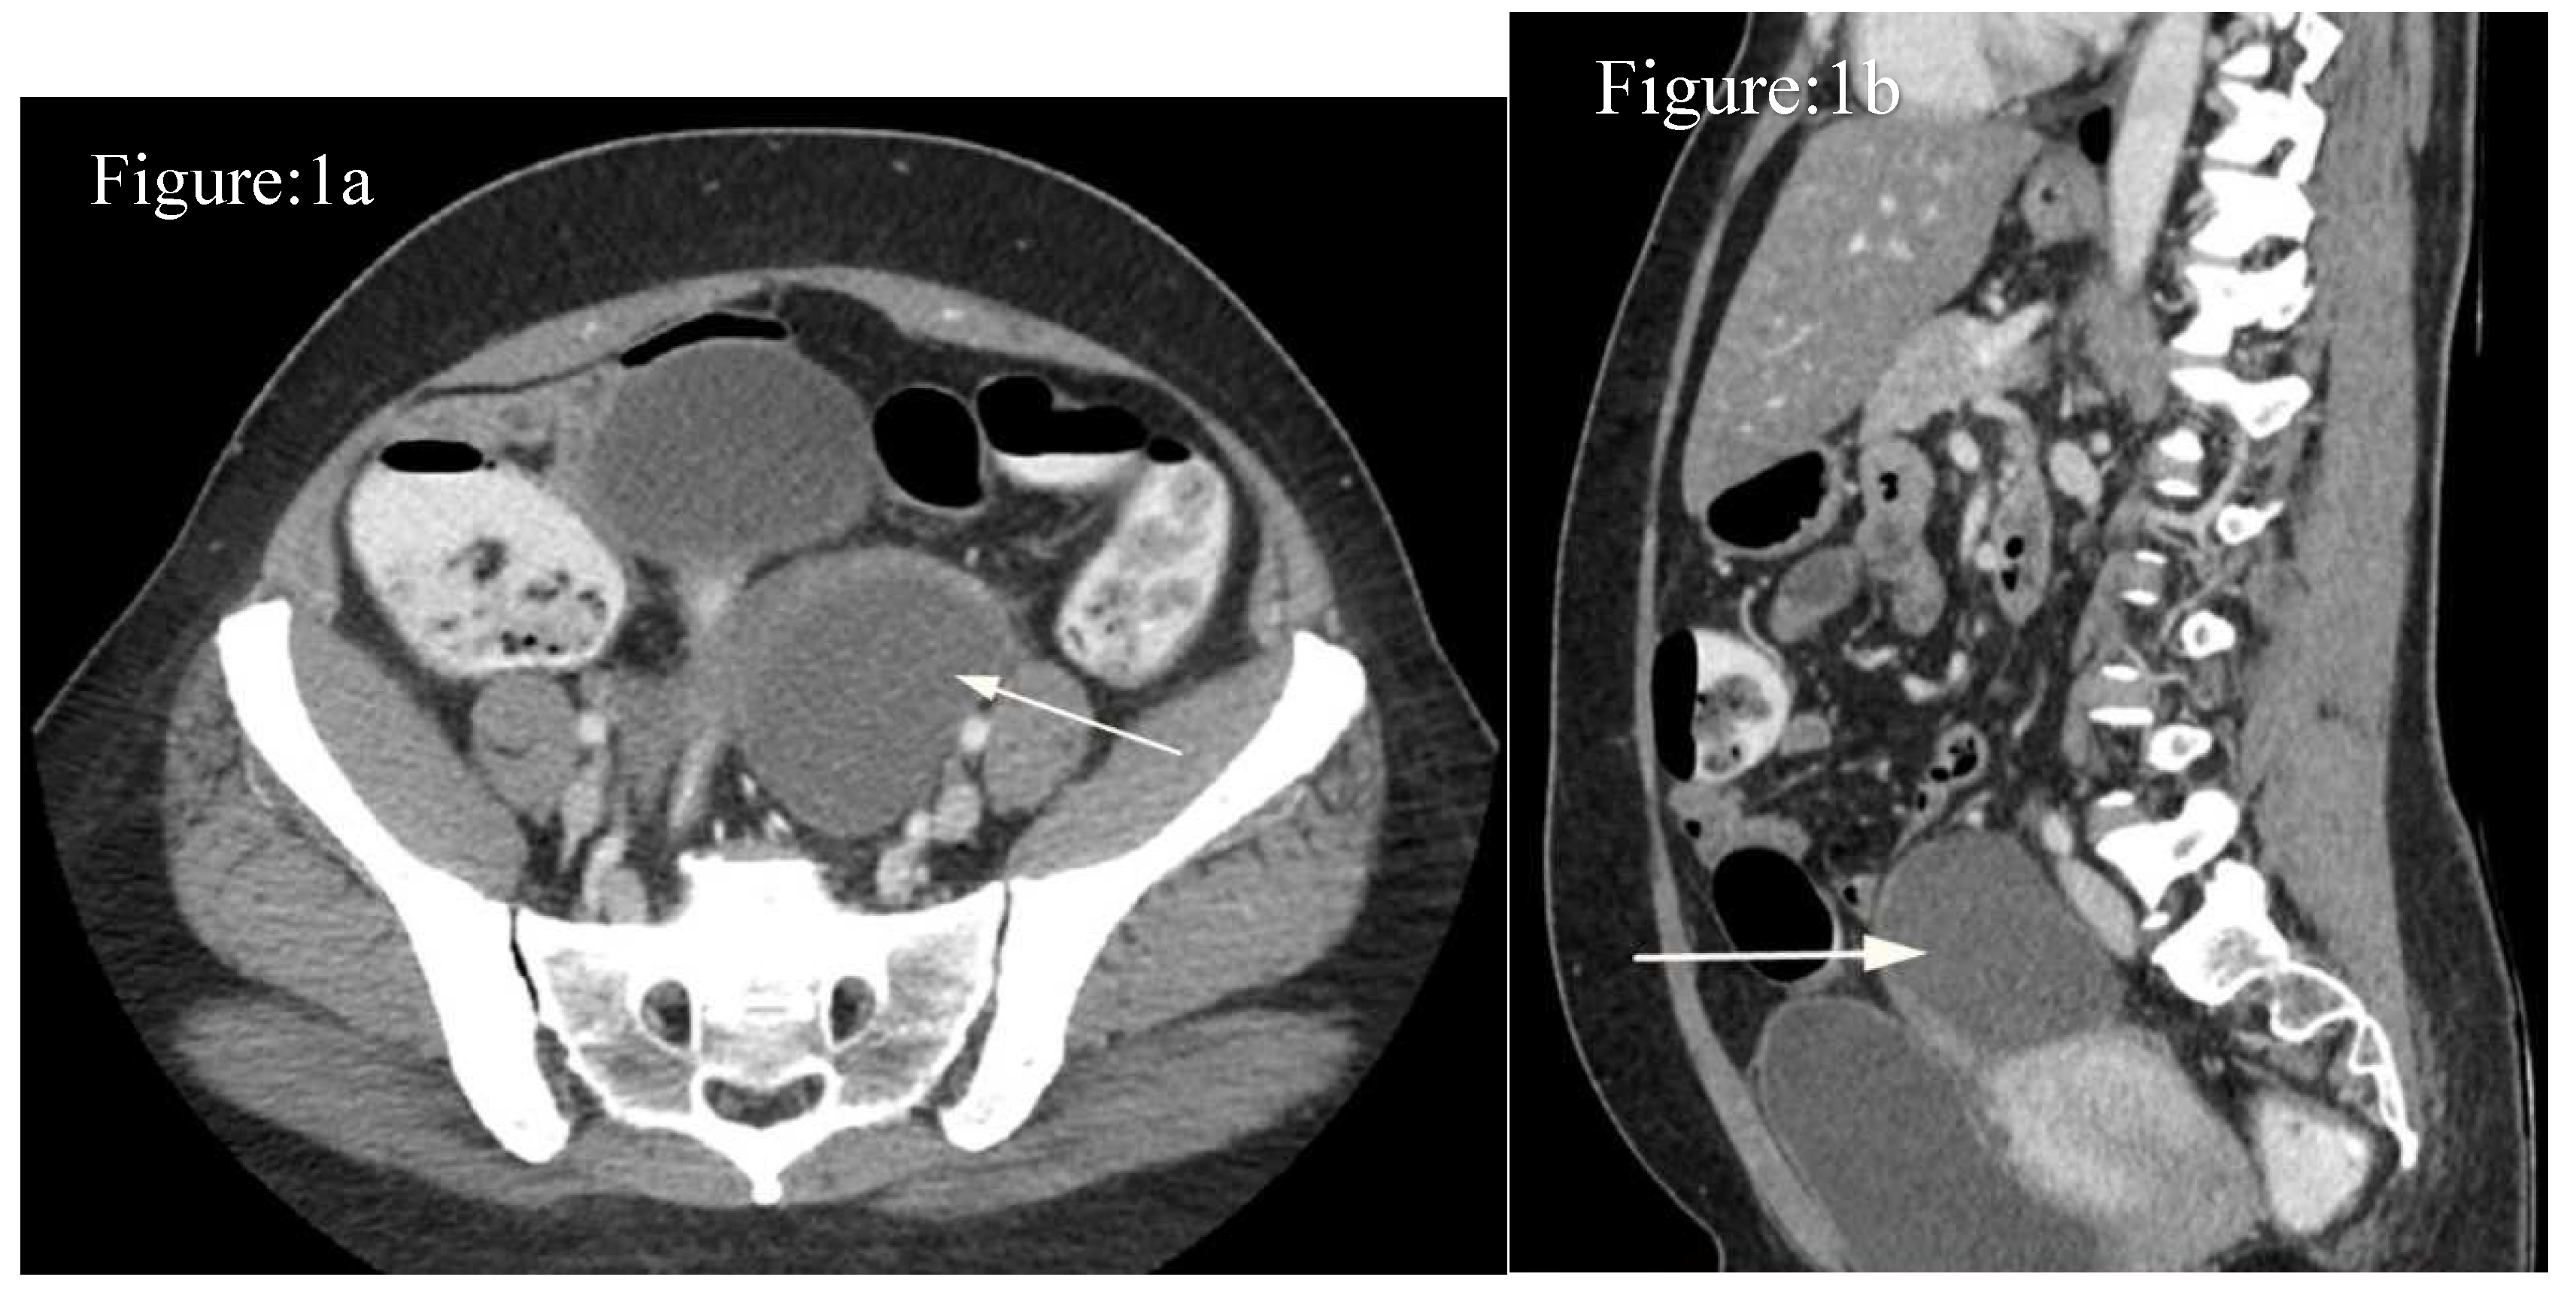

Case-1: